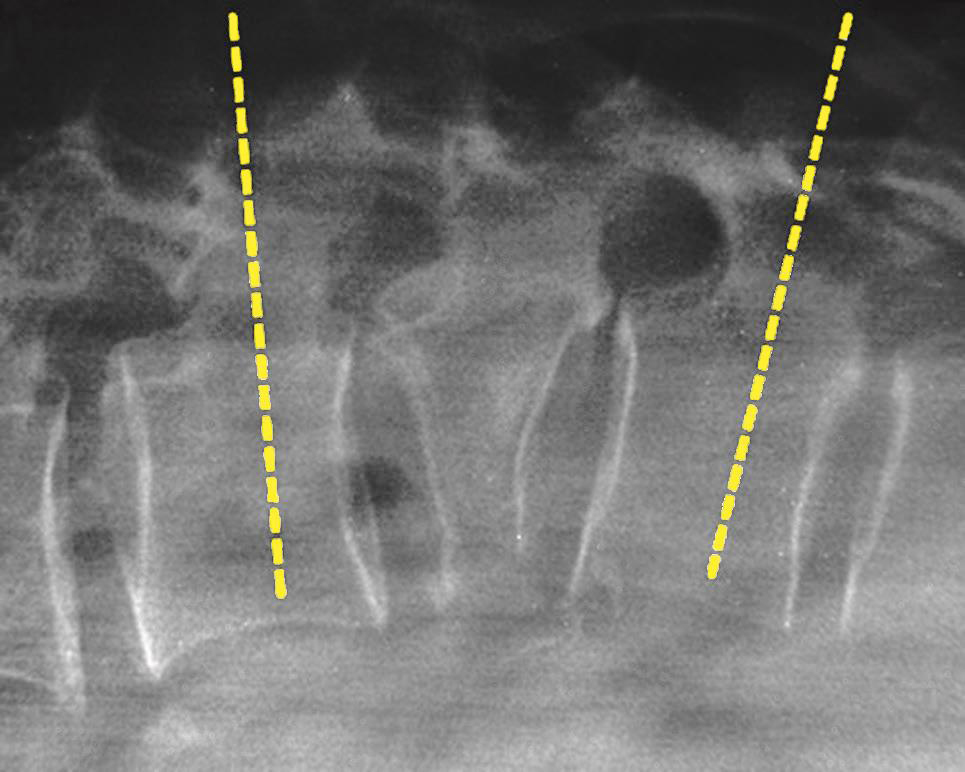

无论什么手术都必须做TOP像扫描,在其上确定手术部位和断层扫描范围。如侧卧位时的椎间隙侧方穿刺入路做脊柱的正位TOP像(图3-3-6),俯卧位时的椎板间入路做脊柱的侧位TOP像(图3-3-7)。

一般的CT机架可以调整角度(图3-3-8),调整机架角度进行扫描是寻找操作平面的关键举措,不同的穿刺途径和手术目的要求机架调整的角度也不同,如L 4/5 经椎间隙侧方入路时,如果手术平面无髂骨阻挡,则采用零度扫描(见图3-3-6A、图3-3-8B),否则为了避开髂骨阻挡,机架应向头侧倾斜(图3-3-6B、图3-3-8C);用于射频靶点消融或内镜髓核摘除的椎板间入路,如果扫描角度与椎间隙平行,将多有椎板阻挡(图3-3-9),其要点在于穿刺靶点为直接突出的椎间盘,而穿刺途径又必须避开椎板经过椎板间隙才能成功,因此要求调整到既能显示靶点又经过椎板间隙的角度,一般向足侧倾斜(图3-3-8A、图3-3-10);椎弓根入路则沿椎弓根轴线扫描(图3-3-11)。